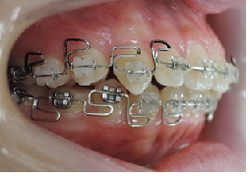

治療は上顎から矯正装置を装着していきます。

その後下顎の矯正装置を装着します。

この過程で歯並びが整いMEAW(マルチループ)を装着しやすくなります。

MEAW(マルチループ)を使用する事で上顎前突(出っ歯)や咬合高径(咬み合わせの高さ)の改善をしています。

☆治療途中

MEAW(マルチループ)を使用する事で上顎前突(出っ歯)や咬合高径(咬み合わせの高さ)を改善して2年6ヶ月で非抜歯での治療で綺麗な歯並びになりました。